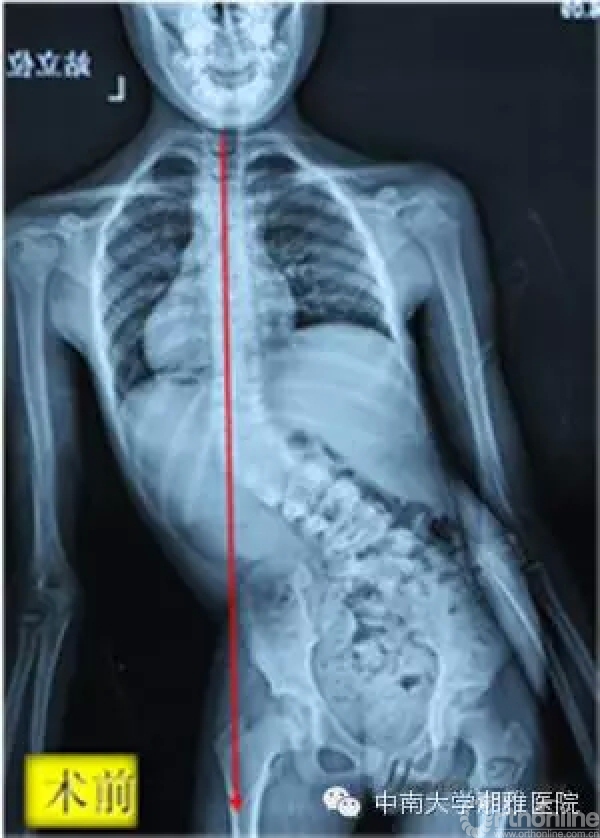

(术前小佳盈的大体照和站立位X片,躯干严重偏斜失衡,需要搀扶才能行走;术后躯干平衡恢复,可自行行走)

小佳盈是一名来自郴州的9岁女孩,3岁时被诊断患有严重的先天性脊柱侧凸,胸12及腰5各有一个半椎体。多年来,父母带着小佳盈走遍了省内的各家医院,但皆因年龄太小,手术难度大、风险高而没有能够解除疾苦。

初次见到小佳盈,张宏其教授就知道眼前这个9岁的女孩脊柱侧凸畸形十分复杂,如不及时手术中止病情进程,不但现有畸形、外观矫正无从谈起,且不出几年小佳盈势必将全瘫。